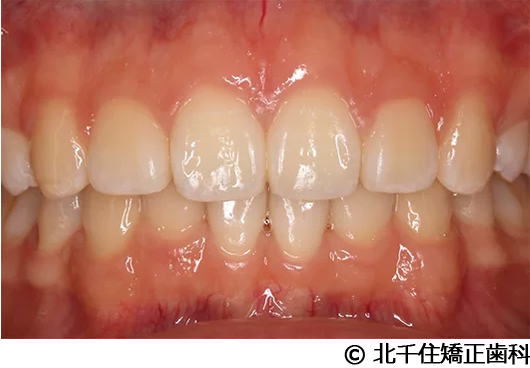

【症例2】上顎前突症

- 治療前

- 治療中

- 治療後

- 治療名

- 上顎前突症

- 費用

- 1,399,000円(税込)

- 期間

- 3年6ヵ月

- 治療回数

- 42回

- 通院頻度

- 1ヵ月ごと

- 年齢・性別

- 19歳10ヵ月・男性(初診時)

治療内容

-

患者様の症状

主訴:出っ歯、口元の突出、横顔をきれいにしたい

治療方法

骨格性の上顎前突、上下顎第一小臼歯4本及び上顎第二大臼歯を抜歯して矯正用アンカースクリューを併用してワイヤー矯正治療(セラミックブラケット)。

治療結果

骨格性上顎前突に対し、抜歯および矯正用アンカースクリューを併用した矯正治療により歯列および咬合関係の調整を行った症例である。治療後は保定装置を使用し、歯列および咬合の安定維持を目的として定期的な経過観察を行っている。

※治療結果は個人差があります。

治療を行う上での注意点(リスク・副作用)

歯磨き不良に伴うカリエスや歯周病、顎関節症、歯根吸収など。